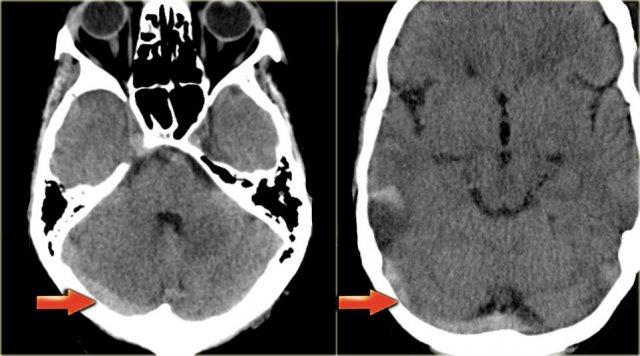

Dấu hiệu cục máu đông tăng tỷ trọng (2)

Hình ảnh tĩnh mạch vỏ não bị huyết khối biểu hiện dưới dạng một dải hoặc đường tăng tỷ trọng hình dây thừng còn được gọi là dấu hiệu dây thừng (cord sign).

Một thuật ngữ khác thường được sử dụng là dấu hiệu mạch máu tăng tỷ trọng (dense vessel sign).

Dấu hiệu cục máu đông tăng tỷ trọng (3)

Hình ảnh bên trái là của một bệnh nhân có nhồi máu xuất huyết ở thùy thái dương (mũi tên đỏ).

Lưu ý xoang ngang tăng tỷ trọng do huyết khối (mũi tên xanh dương).